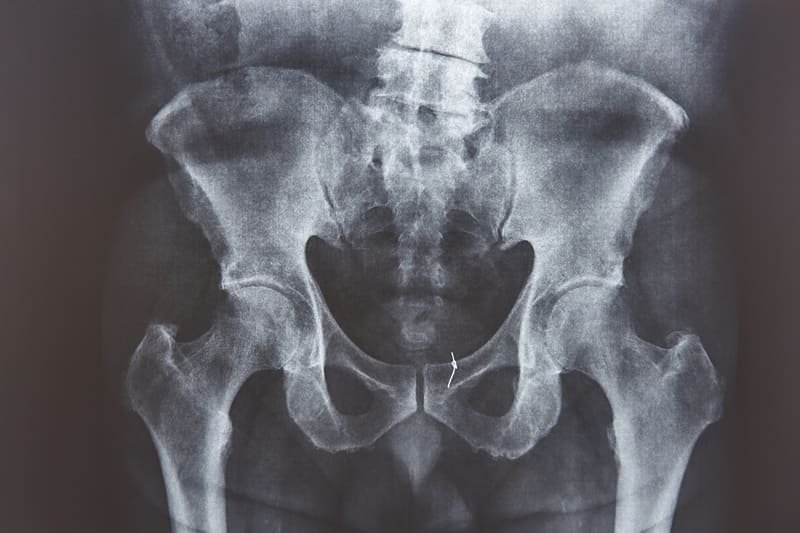

La Radiografía de pelvis en Guadalajara, Jalisco es un estudio esencial para evaluar huesos pélvicos, articulaciones sacroilíacas y caderas ante dolor, traumatismos o sospecha de fractura. Este examen permite identificar desplazamientos, lesiones degenerativas o alteraciones estructurales que afectan la movilidad. La Radiografía de pelvis en Guadalajara, Jalisco se realiza a domicilio con equipo portátil moderno, brindando imágenes digitales claras y un diagnóstico confiable sin que el paciente tenga que trasladarse a una clínica.

La Radiografía de pelvis en Guadalajara, Jalisco se recomienda tras caídas, accidentes, dolor intenso en la cadera o dificultad para caminar. También es útil en pacientes con sospecha de fracturas, luxaciones o desgaste articular relacionado con la edad. Realizar la Radiografía de pelvis en Guadalajara, Jalisco en casa facilita la atención de adultos mayores o personas con movilidad limitada, permitiendo una valoración oportuna y segura en su propio entorno.

Sí, la Radiografía de pelvis en Guadalajara, Jalisco permite identificar fracturas, fisuras y desplazamientos óseos con buena precisión. Es especialmente útil en traumatismos, accidentes o dolor persistente que requiere descartar lesiones estructurales importantes.